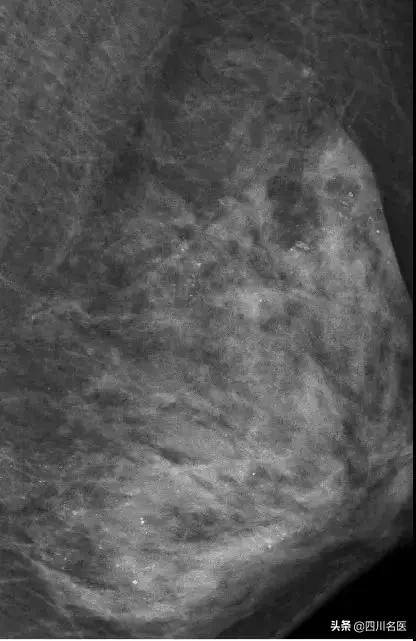

最让医生意外的是她的左侧乳房。乳腺X线检查时,发现里面全部都是细小如沙子一样的钙化灶,布满整个乳腺。

(在X光片下,朱女士的乳腺里满是星星点点的钙化灶)

医生分析,极有可能是按摩师用力不当损伤了腺叶乳管,导致乳腺出现坏死性细小点状钙化。